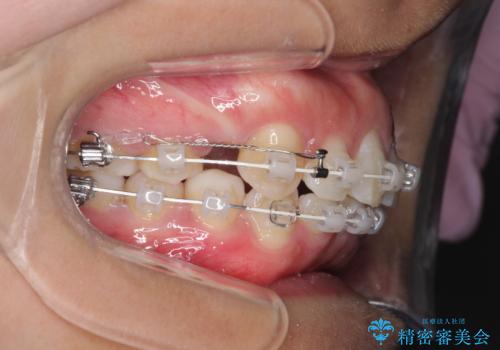

- 矯正装置

- 審美装置

- 出っ歯を主訴に来院されました。

下の歯並びに対して、上の歯が全体的に前方に位置している状態でした。

上の歯の前から4番目の歯を2本抜歯して、そのスペースに前歯を移動させて、前歯を引っ込める計画としました。